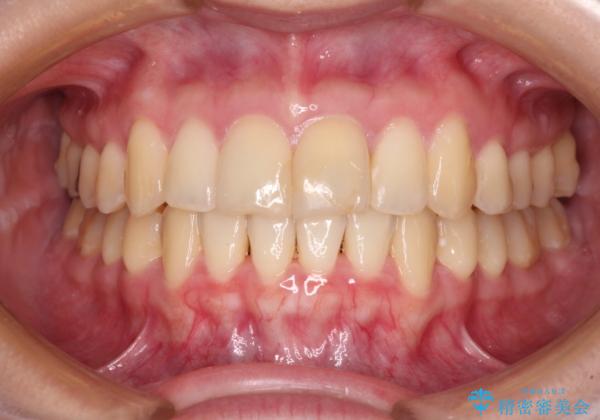

上下前歯のデコボコをきれいに インビザラインによる矯正治療

- 前歯の著しい叢生と前突感を気にして来院された患者様です。

叢生が強いため、事前に前歯をワイヤー矯正で速やかに叢生を解消し、その後はインビザラインにて矯正治療を行うこととしました。

ワイヤー矯正を併用したことで前歯の叢生を速やかに解消することができました。

一方口元の突出感を改善するために時間がかかり、2年超を要しましたが、満足のいく仕上がりとなりました。